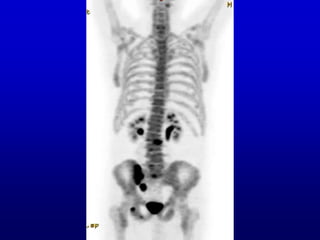

PET scan of brain in epilepsy

PET scan ofbrain in epilepsy

• #9 We’ll come back to the 3D bone scan. For the moment, on the theme of the interface of medical imaging and brain science, here is a nuclear medicine image of the brain in a patient with epilepsy, also a MIP. If you were fortunate enough to attend the last talk, about epilepsy, this is relevant to that. This type of study helps in planning surgery for epilepsy.